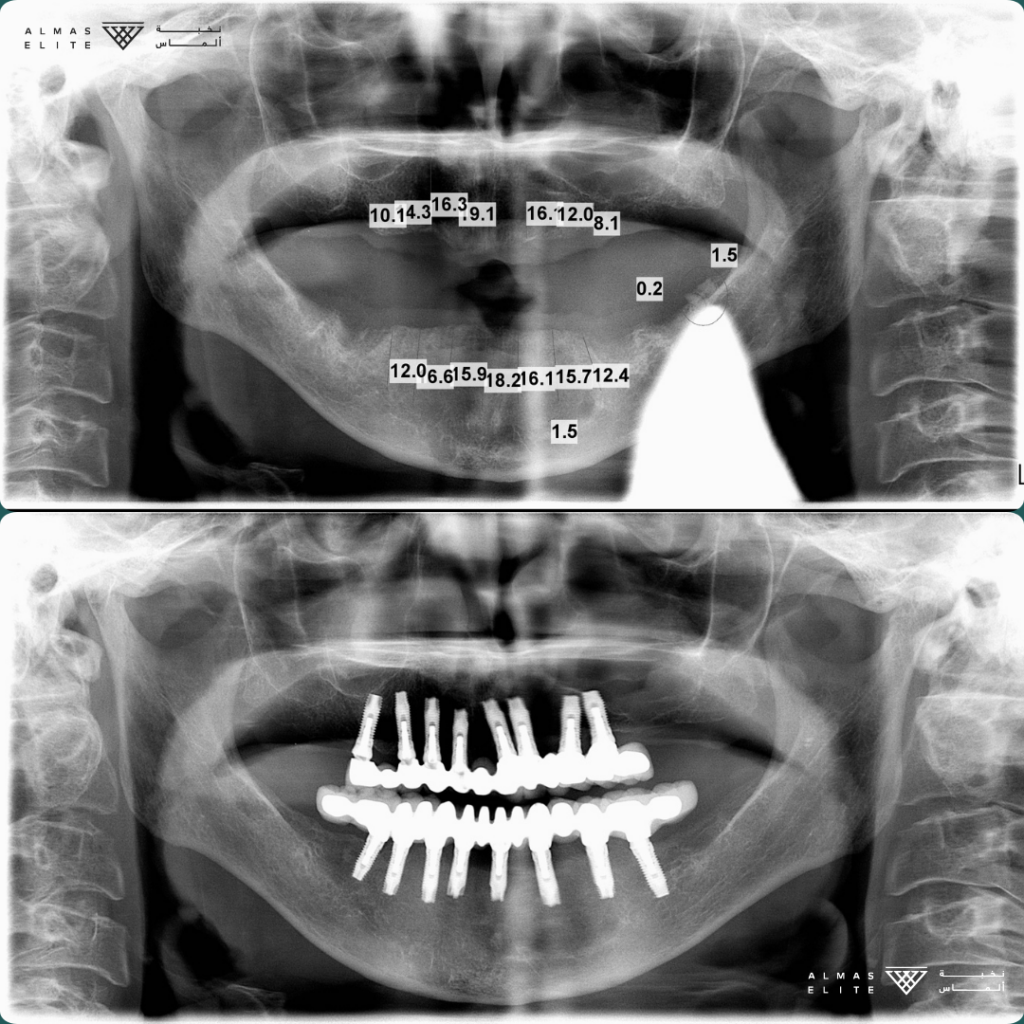

القرار النهائي لملاءمة الزراعة يتم بعد استشارة الطبيب، والفحص السريري، والتصوير الإشعاعي (مثل الأشعة ثلاثية الأبعاد) حسب الحاجة.

• الفحص الكامل: يشمل الأشعة ثلاثية الأبعاد وتحليل جودة وكثافة العظم.

٣) المرحلة الجراحية (Stage 1)

• الزراعة التقليدية: بعد شفاء موضع الخلع بـ 6–8 أسابيع في كثير من الحالات.

• الزراعة الفورية: تتم بعد الخلع مباشرة بشرط توفر المعايير اللازمة.

تليها فترة اندماج عظمي تستغرق من 3 إلى 6 أشهر حسب الحالة الصحية وجودة العظم.

٤) المرحلة التركيبية (Stage 2)

• فتح اللثة وتركيب Healing Abutment فوق الزرعة.

• أخذ المقاسات أو إجراء المسح الرقمي للأسنان.

• تركيب التاج النهائي في العادة خلال أسبوعين تقريبًا من أخذ المقاسات.

المدة المتوقعة للعلاج: من 3 إلى 6 أشهر (قد تختلف من حالة لأخرى).

عدد الزيارات التقريبية: من 4 إلى 6 زيارات حسب الخطة العلاجية.